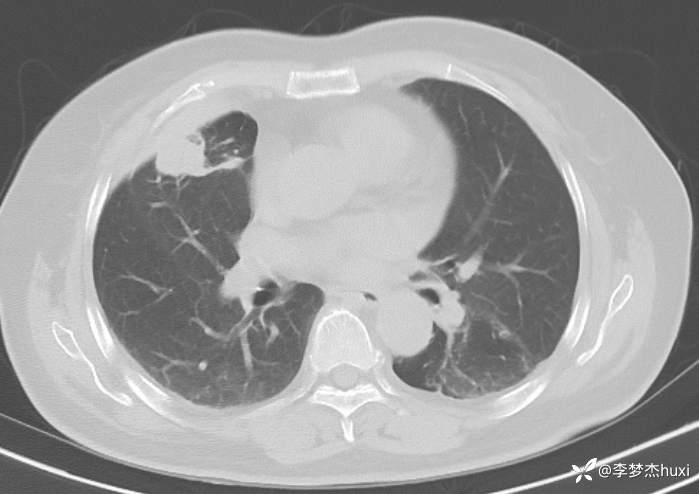

女性69岁,胸痛住院,检查发现肺占位性病变,猜病理

辅助检查:胸部CT:右肺占位?炎症?双肺炎性变,左肺下叶陈旧性病变,双肺纹理增多,主动脉及冠状动脉钙化,双侧胸膜局部增厚,胆囊结石,多发肝囊肿?请结合超声。

临床诊断:肺占位